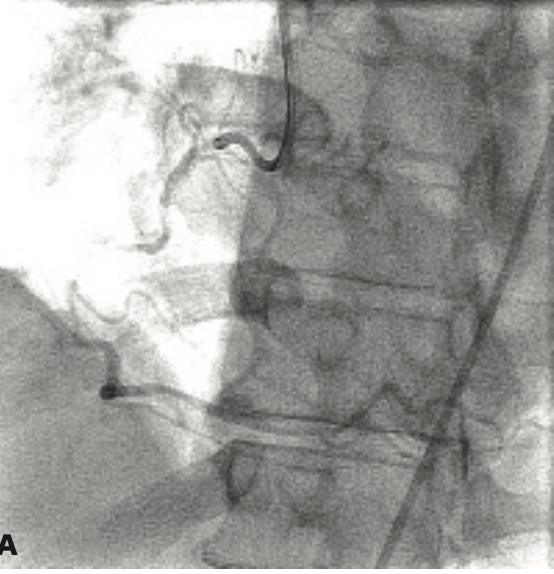

A 72-year-old man presented to the emergency room for chest discomfort consistent with unstable angina. He had a past medical history of hypertension, hyperlipidemia, type 2 diabetes mellitus, and mild aortic stenosis. Cardiac biomarkers were negative. He was stabilized medically and underwent exercise SPECT that showed 10% anterior reversible defect.

Subsequent coronary angiography showed 3-vessel coronary artery disease. He was referred for coronary artery bypass surgery but refused surgery after discussion with the cardiac surgical team. Therefore, he returned to the cardiac catheterization laboratory for percutaneous coronary intervention.